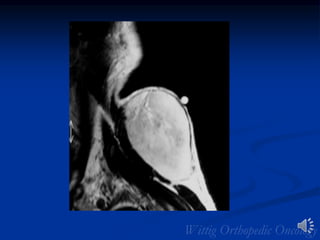

MRI Synovial Sarcoma of Shoulder

Bone Involvement

• Intermuscular near

large joint

• Foot or ankle

• May be ill- or well-

defined

• Ca+2 in 1/3 (lung

metastases may also

Ca+2)

• Osseous involvement in

11-20%

Synovial Sarcoma Imaging

• Large lesions often

very heterogeneous on

T2

• Triple signal intensity

pattern suggestive

• Cluster of grapes

(septated/multilocular)

• Hemorrhage/fluid

levels/cystic areas

Synovial Sarcoma: Heterogeneous

Enhancement